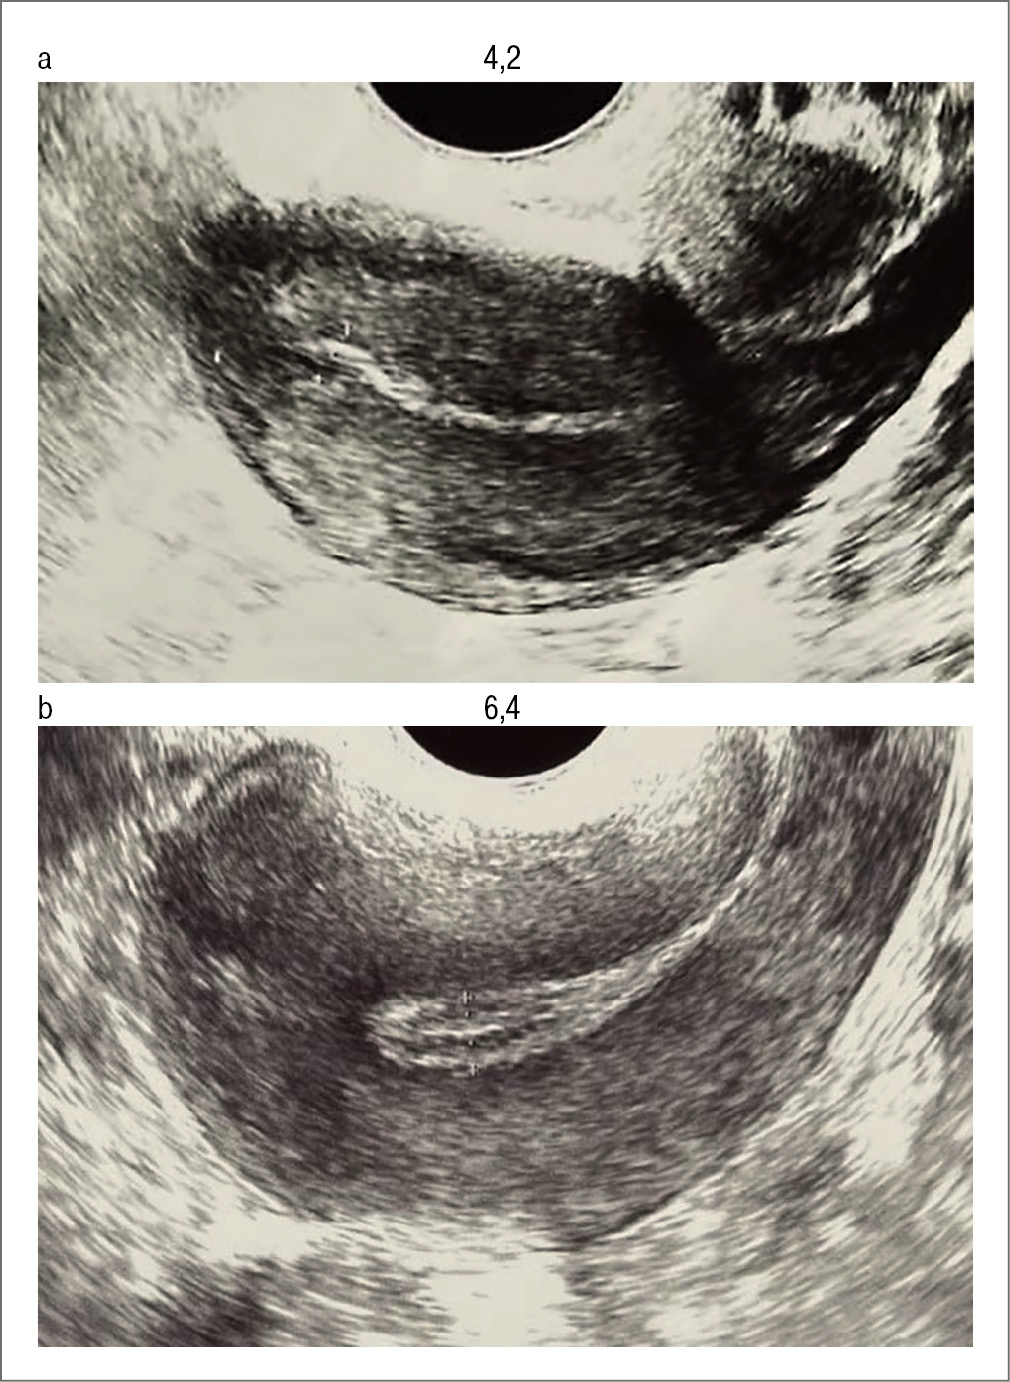

В мае 2022 г. проведена однократная процедура внутриматочного воздействия безабляционным эрбиевым лазером. Через месяц после процедуры на 9-й день цикла проведена пайпель-биопсия эндометрия, исследование которого выявило активную пролиферацию желез эндометрия, отсутствие склероза, диффузную экспрессию VEGF в сосудах и межклеточном матриксе, а также выраженную экспрессию ЭР и ПР в >90% железистых клеток и стромы. Толщина эндометрия в середине менструального цикла по данным УЗИ до процедуры составила 4,2 мм, после – 6,3 мм (рис. 8). В августе 2022 г. произвели перенос РЭ в полость матки. В настоящее время (02.2023) беременность прогрессирует.

Рис. 8. Толщина эндометрия (мм) в середине менструального цикла по данным УЗИ до (а) и после (b) лазерной процедуры.

Fig. 8. Endometrial thickness (mm) in the middle of the cycle according to ultrasound before (a) and after (b) the laser procedure.